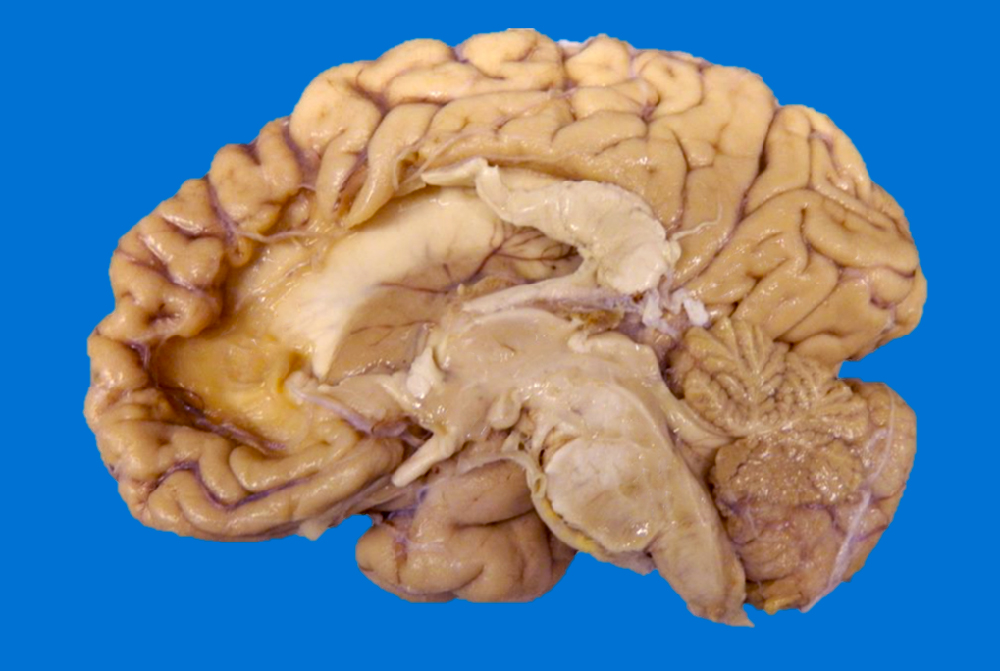

Gross description

- < 8 hours to 48 hours

- Congestion of gray matter and edema (Histopathology 2011;58:333)

- Dusky discoloration and blurring of the gray-white matter junction

- Ill demarcated borders

- Reperfusion of an ischemic lesion where vessels are also affected can become hemorrhagic (Stroke 1986;17:586)

- Hemorrhagic discoloration can be limited to a specific vascular territory

- Commonly observed as secondary infarcts in the setting of brain herniations (e.g., obstruction of pericallosal artery in subfalcine herniation, obstruction of posterior cerebral artery in uncal herniation)

Gross images

Sample pathology report

- Brain, autopsy:

- Acute infarct, 10.5 x 6 x 4 cm, left frontal, temporal, parietal lobes (see comment)

- Gross description: External examination of the cerebrum shows a 10.5 x 6 cm area with marked vascular congestion, narrowing of the sulci and softening extends from the left frontal lobe to the superior temporal lobe and parietal lobe. The area of softening spares the superior frontal gyrus. At the base of the brain, severe atherosclerosis is observed in the left middle cerebral artery with > 90% of stenosis.

- On coronal sections, this area is characterized by mild dusky discoloration in the cortical ribbon and in the subjacent white matter with blurring of the gray-white matter junction measuring up to 4 cm in depth. The adjacent left lateral ventricle shows decreased caliber compared with the right lateral ventricle.

- Microscopic description: Low power examination of the frontal, parietal and temporal cortices show marked vacuolation of the neuropil and pericellular retraction artifact. On high power, the neurons are remarkable for cell shrinkage, hypereosinophilic perykarya and loss of demarcation of the nuclear contours. The subjacent white matter is pale with vacuolization and poorly demarcated from the gray matter.

- Comment: The observed distribution of the infarct corresponds to the left MCA vascular territory.